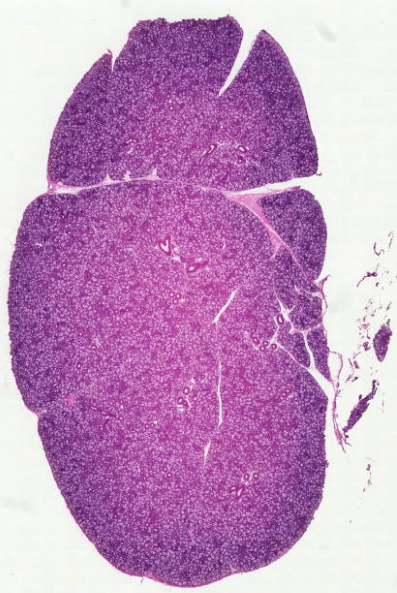

Красный костный мозг

Red bone marrow

مغز قرمز استخوان